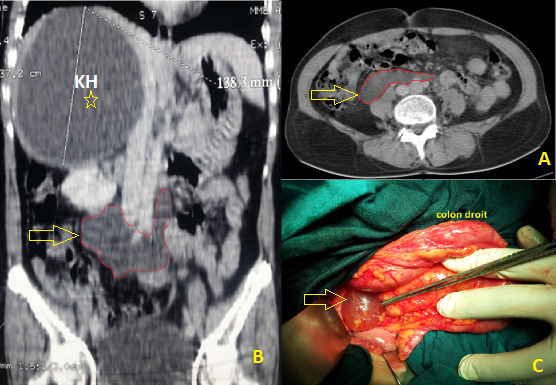

Les kystes mésothéliaux simples sont rares et bénins. Leur pathogénie reste mal élucidée ; Il semble qu'ils sont du à un défaut congénital d'accolement des surfaces péritonéales. Souvent pauci-symptomatiques, Leur découverte peut se faire ainsi fortuitement à l'imagerie, posant alors un problème de diagnostic différentiel par rapport aux autres formations kystiques péritonéales. Seul l'examen anatomopathologique de la pièce opératoire permet de confirmer le diagnostic. Nous rapportons l'observation d'une patiente âgée de 55 ans, sans antécédents notables, admise dans notre service pour prise en charge d'un kyste hydatique du foie : douleur de l'hypochondre droit et image typique à l'échographie d'un kyste hydatique de type 2 (classification de Gharbi) de 14 cm de diamètre, occupant le lobe droit hépatique. Le scanner abdominal réalisé pour une meilleure caractérisation topographique de ce kyste hydatique met en évidence, en plus de ce dernier, une image kystique à contenu liquidien et à paroi non rehaussée après injection de produit de contraste. Elle occupe la région rétro-péritonéale médiane et mesure 9 cm au grand axe (A,B). Vu le contexte clinique, ce kyste aspécifique a été considéré initialement comme une seconde localisation hydatique. L'intervention chirurgicale a été conduite par voie sous costale droite. Un traitement conservateur du KH hépatique a été réalisé dans un premier temps. Ensuite, un décollement colo-pariétal droit fait découvrir un kyste rétro-péritonéal à paroi mince translucide et à contenu séreux (C). Une énucléation de ce kyste a été réalisée. L'examen anatomopathologique porte le diagnostic de kyste mésothélial simple. Le pronostic de cette pathologie bénigne reste excellent avec un risque de récidive nul après exérèse chirurgicale complète.